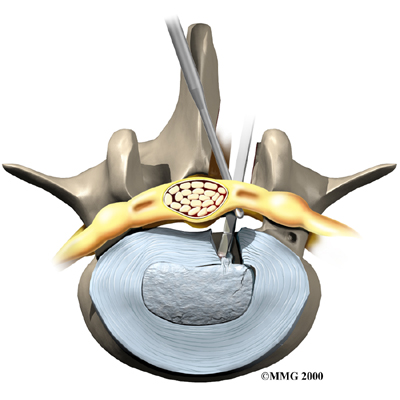

Microdiscectomy

Microdiscectomy is becoming the standard surgery for lumbar disc herniation. The procedure is used when a herniated disc is putting pressure on a nerve root. It involves carefully taking out part of the problem disc (discectomy). By performing the operation with a surgical microscope, the surgeon only needs to make a very small incision in the low back. Categorized as minimally invasive surgery, this surgery is thought to be less taxing on patients. Advocates also believe that this type of surgery is easier to perform, that it prevents scarring around the nerves and joints, and that it helps patients recover more quickly.

Related Document: FYZICAL De Zavala's Guide to Lumbar Discectomy